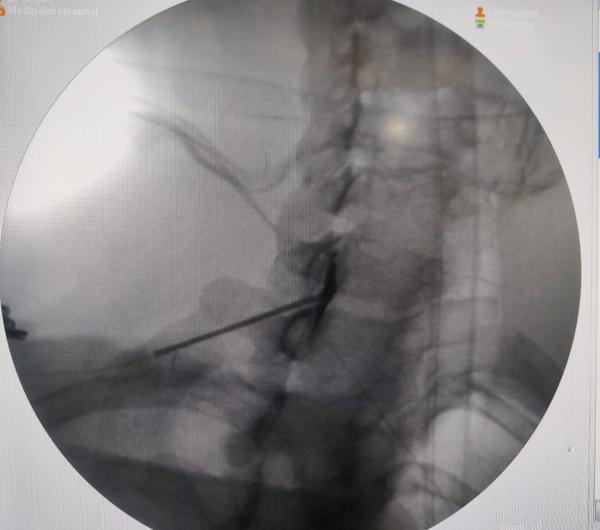

Spine injections, also known as epidural steroid i...